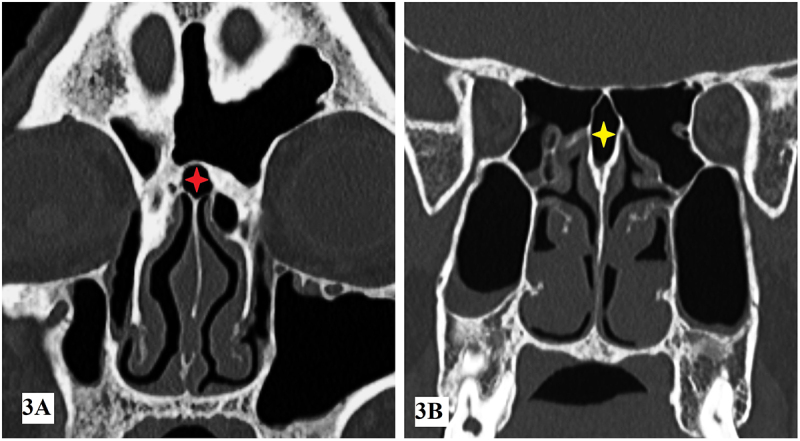

Abstract Image